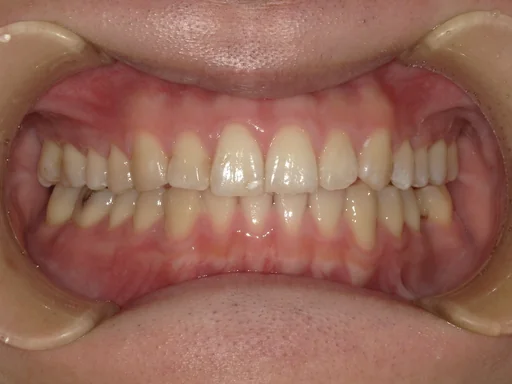

症例2

こちらは、インビザラインによる矯正治療の症例です。

治療前は歯並びの乱れが見られましたが、マウスピースを段階的に交換しながら歯を動かすことで、見た目だけでなく噛み合わせも改善しました。

インビザラインは、目立ちにくく取り外しが可能なため、日常生活への影響を抑えながら治療を進められるのが特長です。